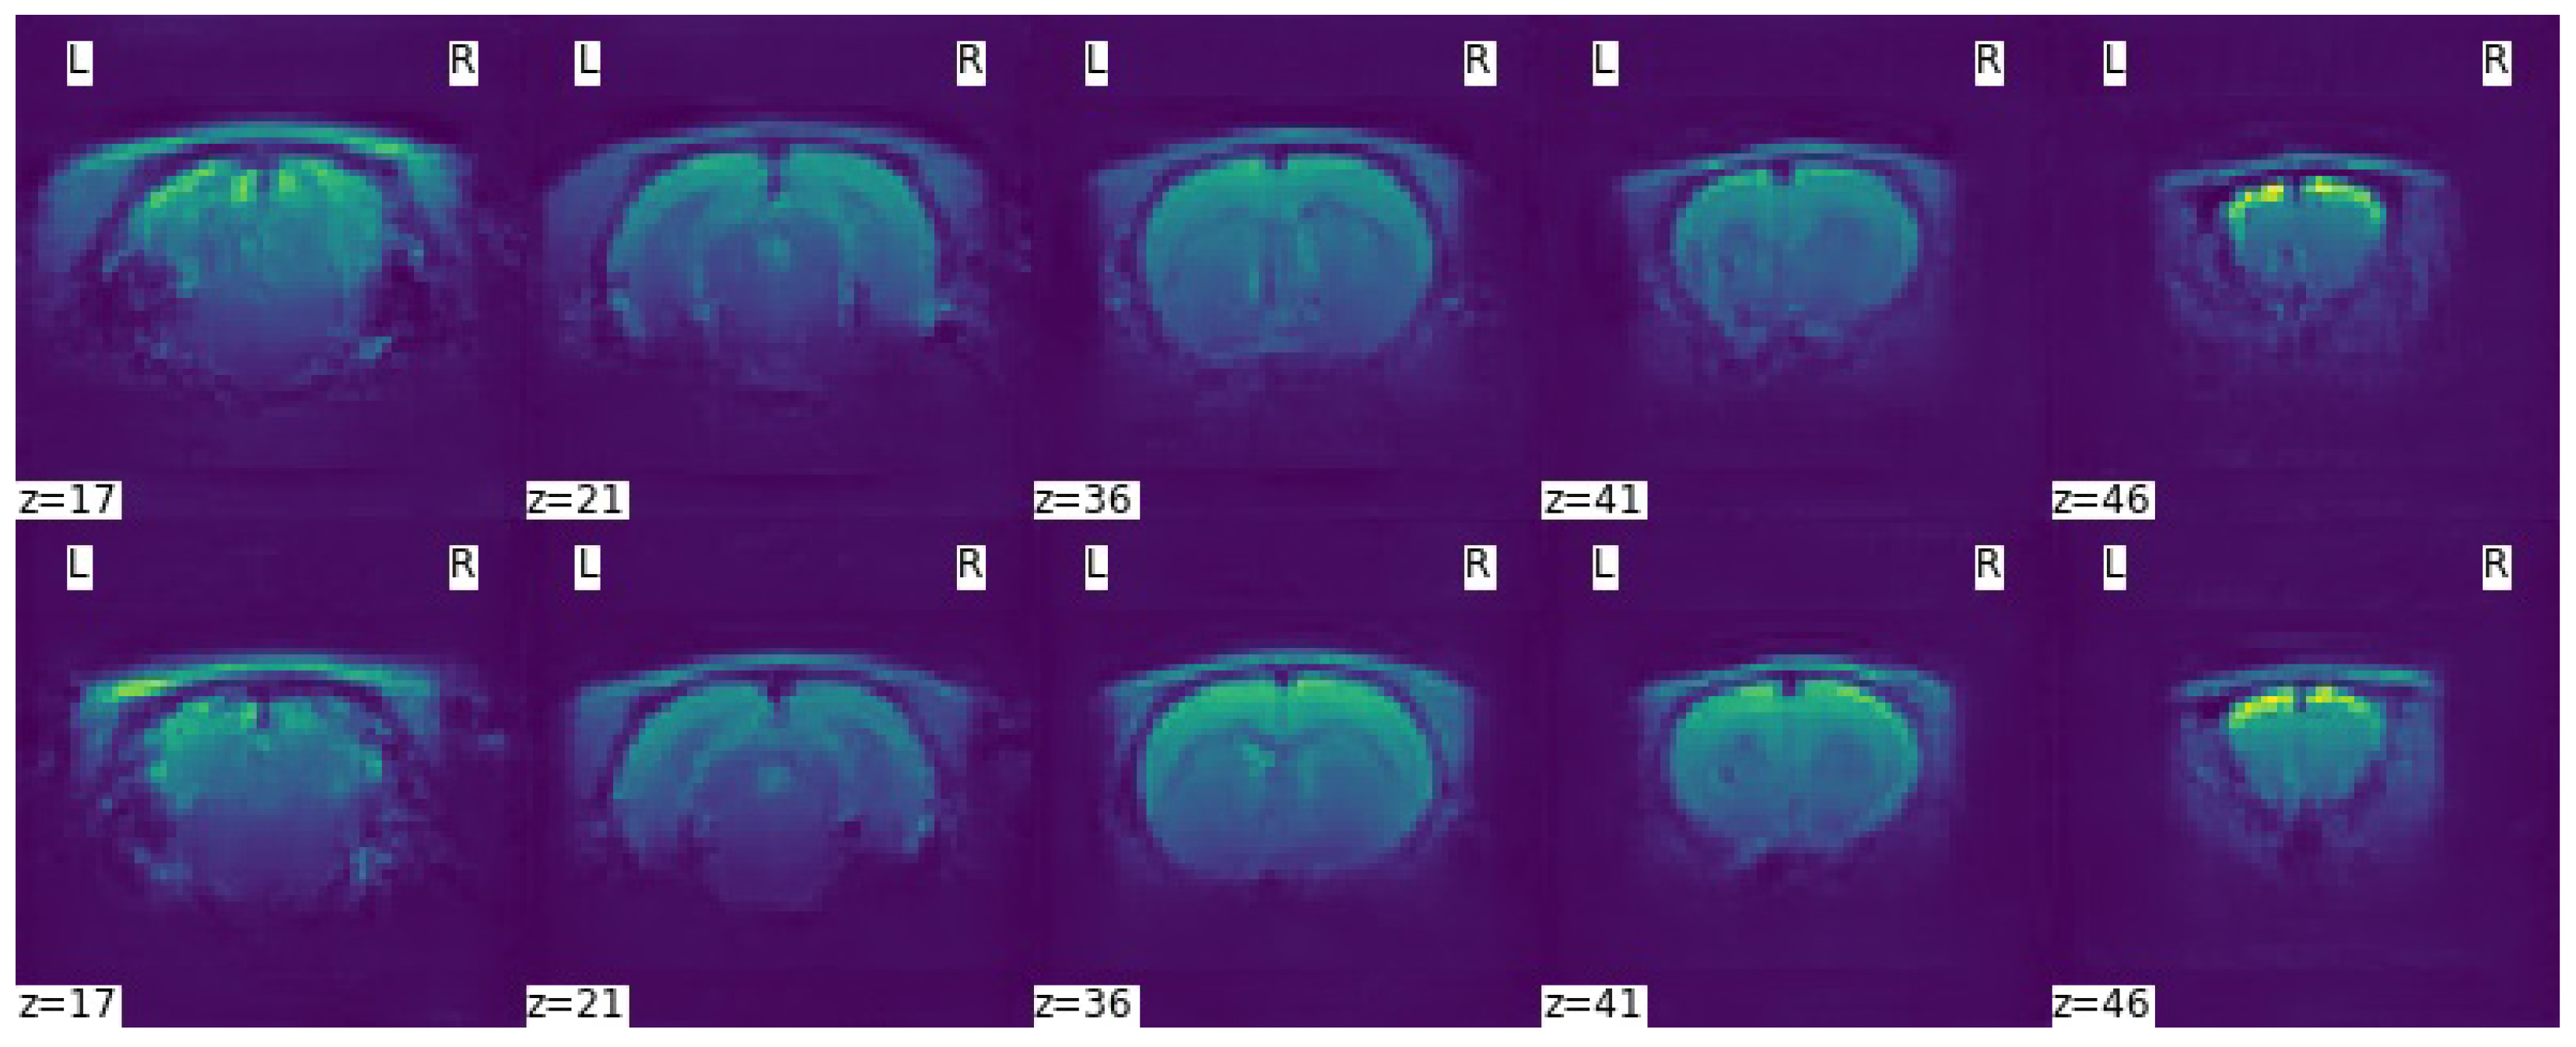

| Tests | Test1 | Test2 | Test3 | Test4 | Test5 | Test6 | Test7 | Test8 | Test9 |

|---|---|---|---|---|---|---|---|---|---|

| Data sets | Dr174 | Dr174 Ds87 | Dr174 Ds174 | Dr174 Ds261 | Dr174 Ds348 | Ds174 | Ds348 | Dr87 Ds174 | Dr87 Ds348 |

| Global | 0.8969 | 0.9138 | 0.9083 | 0.9078 | 0.9141 | 0.8238 | 0.7646 | 0.8979 | 0.8259 |

| GM | 0.9381 | 0.9419 | 0.9384 | 0.9376 | 0.9412 | 0.8863 | 0.8586 | 0.9316 | 0.8863 |

| WM | 0.8969 | 0.9077 | 0.9037 | 0.9014 | 0.9098 | 0.8202 | 0.7262 | 0.8897 | 0.8301 |

| CSF | 0.7468 | 0.8232 | 0.8098 | 0.8170 | 0.8180 | 0.6095 | 0.4418 | 0.7442 | 0.6273 |